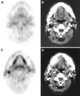

Metastasis from tumor of head and neck